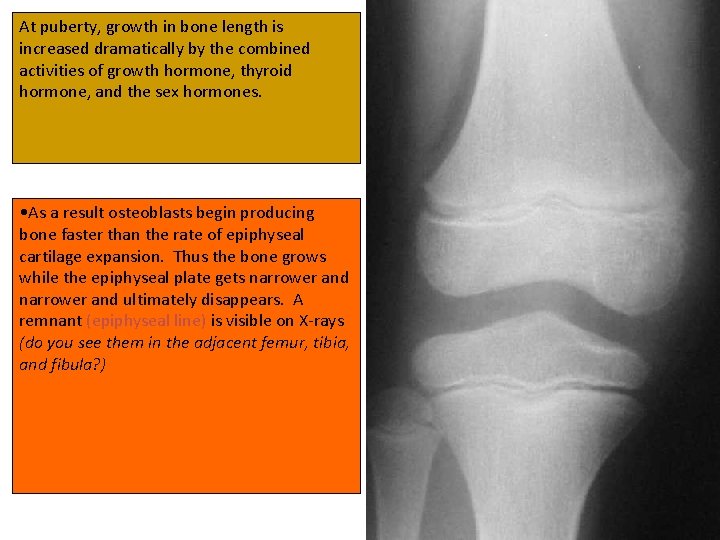

At puberty, growth in bone length is increased dramatically by the combined activities of growth hormone, thyroid hormone, and the sex hormones. • As a result osteoblasts begin producing bone faster than the rate of epiphyseal cartilage expansion. Thus the bone grows while the epiphyseal plate gets narrower and ultimately disappears. A remnant (epiphyseal line) is visible on X-rays (do you see them in the adjacent femur, tibia, and fibula? )